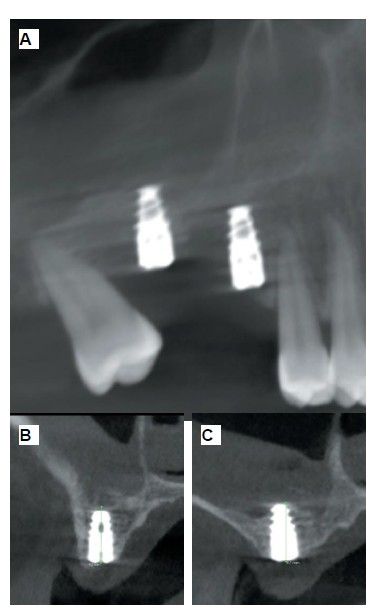

Six months after the maxillary sinus elevation surgery, re-entry was performed for the placement of implants. A 3 x 7mm bone tissue biopsy was obtained using a trephine, and histomorphometric analysis was requested, revealing 30.56% vital bone (Figure 7). After the biopsy sample was taken, two bone level Naturactis implants from ETK® (ETK Implants S.L, Sant Boi de Llobregat, Spain) were placed with an insertion torque of 35 Ncm, and their correct positioning was confirmed in the immediate postoperative period by means of a periapical radiograph (Figure 8). Six months after the placement of the implants, the patient was able to attend for the second stage to place healing abutments. A verification CBCT was performed to assess the final bone height, revealing an increase of 4.2 mm in the region of 1.6 and 6.1 mm in the region of 1.7 (Figure 9).